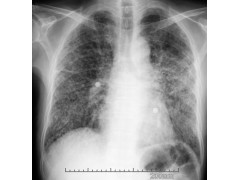

肺纤维化,即肺脏间质组织由胶原蛋白、弹性素及蛋白醣类构成,当成纤维细胞受到化学性或物理性伤害时,会分泌胶原蛋白进行肺间质组织的修补,进而造成肺脏纤维化;即肺脏受到伤害后,人体修复产生的结果。肺纤维化多在40~50岁发病,男性多发于女性。呼吸困难是肺纤维化最常见症状。轻度肺纤维化时,呼吸困难常在剧烈活动时出现,因此常常被忽视或误诊为其他疾病。当肺纤维化进展时,在静息时也发生呼吸困难,严重的肺纤维化患者可出现进行性呼吸困难。其他症状有干咳、乏力。部分患者有杵状指和发绀。肺组织纤维化的严重后果,导致正常肺组织结构改变,功能丧失。当大量没有气体交换功能的纤维化组织代替肺泡,导致氧不能进入血液。患者呼吸不畅,缺氧、酸中毒、丧失劳动力,严重者最后可致死亡。关于,肺纤维化的症状,肺纤维化信息,肺纤维化哪家好还有更多信息等你看哦